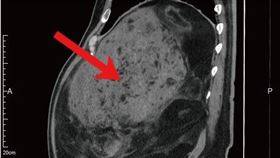

瘤比嬰兒大!6旬男開刀取出22公斤

68歲的楊先生曾有心肌梗塞,積極透過飲食控制和運動減...